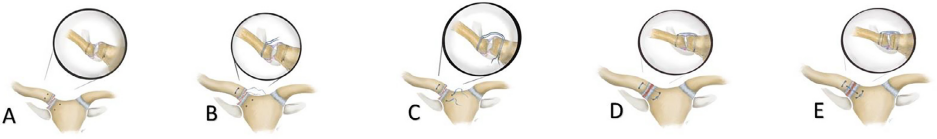

在距SCJ线1 ~ 1、5 cm处,从胸骨柄前皮质至胸骨柄后皮质垂直方向钻取2个2.5mm骨隧道。与锁骨胸骨侧相似,在距关节线2 cm处,从前皮质向后皮质方向垂直钻取2.5 mm的骨隧道。这些隧道平行于锁骨的纵轴,彼此间隔至少1厘米,以便在它们之间有足够的骨桥(图1A)。不可吸收的ETHIBOND EXCEL (R) (Ethicon US, LLC)编号5的缝线平行穿过四个孔。

缝线首先从锁骨上孔穿出,从后向前的方向穿过。然后以相反的方向进入锁骨下孔。此时缝线的上端被置于柄上孔,由后向前;相应的,锁骨缝线的下端被放置在胸骨柄的下孔,在前后方向(图1B,C)。实现了缝线的平行穿过骨隧道。然后,通过牵拉缝线两端进行锁骨后部复位(图1D)。

距离前侧骨隧道至少1 cm再钻取2个骨隧道。第1个孔位于柄部,第2个孔位于锁骨部,从前侧皮质向后侧钻孔。将不可吸收的ETHIBOND EXCEL (Ethicon US, LLC) 5号缝线从以上两个骨隧道穿过,以稳定SCJ在上下方向(图1E)。

图1所示。本文介绍了该技术的手术步骤.

A:从胸骨柄的前皮质到后皮质,沿垂直方向钻两个骨隧道。类似于锁骨的胸骨侧,两个垂直的骨隧道从前皮质向后皮质钻。

B、C:一条不可吸收的缝线平行穿过四个孔。

D:实现了缝线的平行配置。然后,通过牵拉游离缝线边缘进行锁骨的后向平移。

E:另外两个钻孔,第一个在胸骨柄,第二个在锁骨,在前面的骨隧道之间从前皮质到后。不可吸收的缝线被放置在一个简单的构型,以稳定SCJ在上下方向。